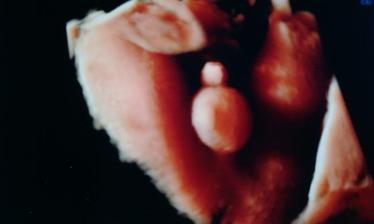

@popoluska35 aj Liamko sa najprv schovával ale pán doktor ho zobudil a potom chudáčik tak zýval ale aspoň sa dal pekne pofotiť ale ako prvú sme mali fotku pipíka 🙂

@xen21 veľmi kvalitné sono to bolo ale povedal aj pán doktor že je lepšie robiť takto fotočky lebo už je bábätko baculatejšie 🙂